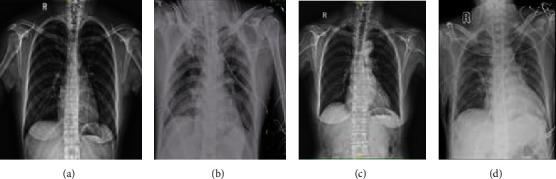

Fifty-seven patients who underwent thoracoscopic mitral valve surgery between July 2019 and December 2019 were selected. The patients were randomly divided into the control (Con) group ( = 28) and the dexmedetomidine (DEX) group ( = 29) using the random number table method. Arterial blood gas analyses were performed, and the oxygenation (PaO/FiO) and respiratory indexes (P(A-a)O/PaO) were calculated 5 min after tracheal intubation (T1), 2 h after operation (T2), 6 h after operation (T3), and 24 h after operation (T4). Moreover, the serum cytokines interleukin-6 (IL-6), tumor necrosis factor- (TNF-), and intercellular adhesion molecule-1 (ICAM-1) were detected using the enzyme-linked immunosorbent method at all time points. Chest radiography was performed 24 h after surgery. Peripheral blood samples were collected before and after the operation for a complete hemogram. Additionally, the procalcitonin concentration was measured and recorded when the patients were transported to the intensive care unit (ICU). The postoperative extubation time, length of ICU stay, and pulmonary infection rate were also recorded.

Inflammatory reaction after surgery was evident. However, the inflammatory cytokines IL-6, TNF-, and ICAM-1 in the DEX group were lower than those in the Con group after surgery (T2 to T4; < 0.05). Neutrophil counts and procalcitonin concentration were higher in the Con group than in the DEX group ( < 0.05). In addition, in the DEX group, pulmonary exudation on chest radiography was lower, and pulmonary function, as shown by an increase in oxidation index and decrease in the respiratory index, improved after surgery ( < 0.05). Moreover, the duration of mechanical ventilation in the Con group was 3.4 h longer than that in the DEX group.

术后炎症反应明显。然而,DEX组术后(T2至T4)炎症细胞因子IL-6、TNF-α和ICAM-1低于Con组(P < 0.05)。Con组中性粒细胞计数和降钙素原浓度高于DEX组(P < 0.05)。此外,DEX组胸部X线显示肺渗出较少,术后肺功能改善,表现为氧合指数升高和呼吸指数降低(P < 0.05)。而且,Con组机械通气时间比DEX组长3.4小时。